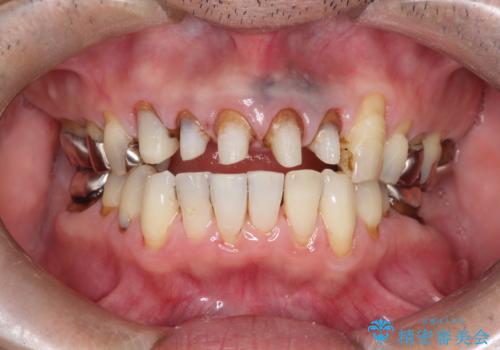

上の前歯の根元が黒い 根の治療を含めたセラミック再治療

- 上の前歯の根元が黒くなっているので、再治療をしたいとのことで来院された患者様です。

レントゲンを撮影すると、適合不良のかぶせ物が装着されており、根の治療も不十分であることが確認されました。

適合不良のかぶせ物をすべて除去して、根の中の治療から再治療を行うこととなりました。

適合不良のかぶせ物が装着されていた歯は、内部がやはり虫歯になっていました。

かぶせ物だけではなく見えないところも、精密な治療をすることが重要となります。